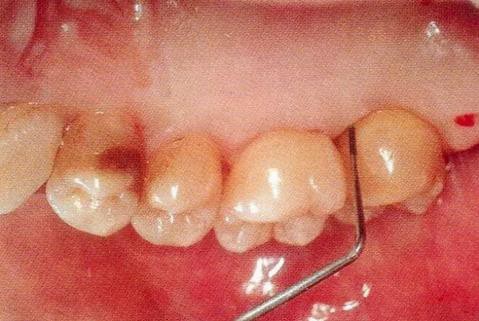

▼圖13-1 近中顎側(cè)術(shù)前牙周探診值是8mm。